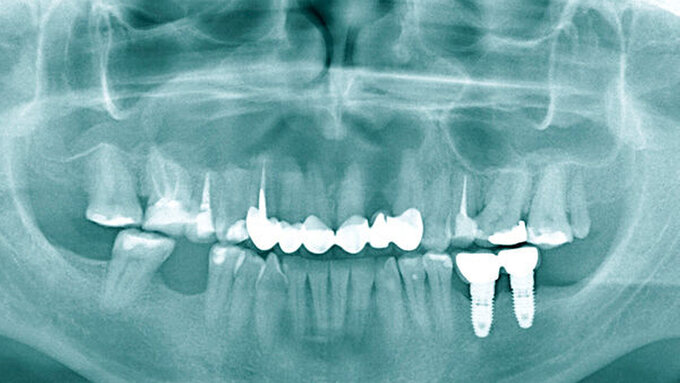

Die pathologische Untersuchung bestätigte die klinische Diagnose durch das Vorhandensein einer respiratorischen Schleimhaut beziehungsweise eines Epithels. Der Defekt wurde mit einer Membran gedeckt, die Wunde dicht vernäht. Zur Kontrolle nach der Wurzelresektion und den Zystektomien wurde ein OPG angefertigt (Abbildung 5). Der Patient erhielt für fünf Tage eine Antibiose. Darüber hinaus wurden Nasentropfen verschrieben und ein Schnäuzverbot erteilt.